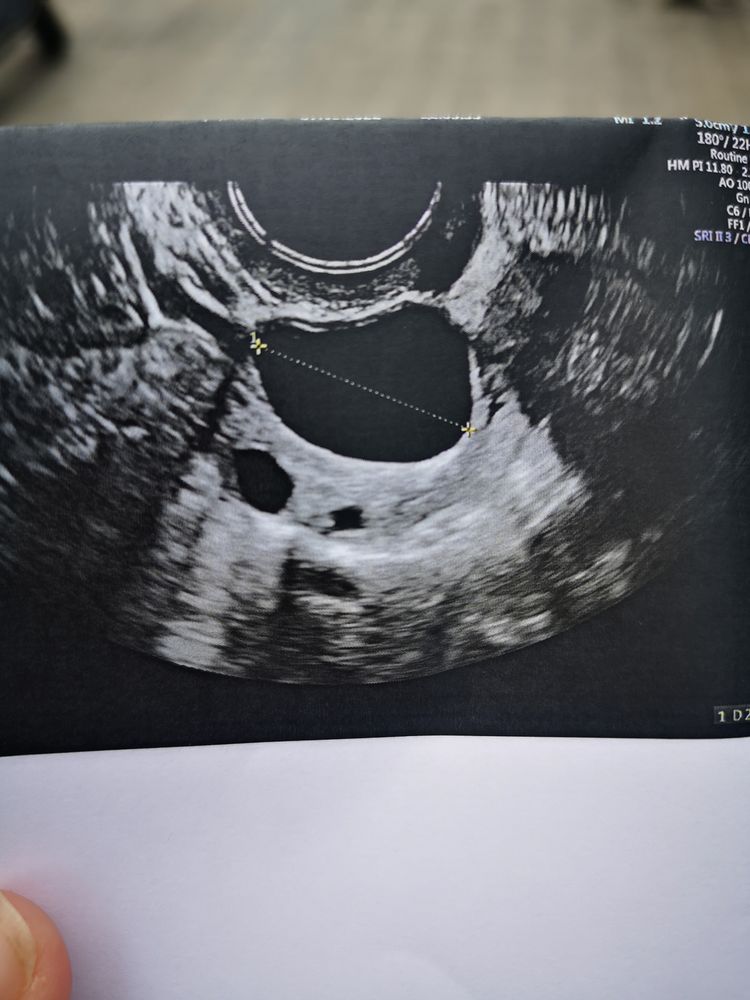

Девочки нужна помощь. Стимуляция летрозолом, 2 таб в день с 3 по 7 дц. В пятницу дф 17.5 и 12 мм. Сегодня 26 мм и 16.7 мм. Тесты на О молчат. Первый раз такое. Можно ли уколоть Овитрель или уже поздно колоть когда 26 мм?

А может он не 26 мм? Я смотрю фоликул не ровный, а он его померял только по диагонали. Обычно меряют щирину и длину и потом делят на 2.